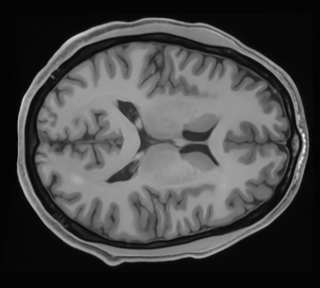

Structural brain MRI data from the Human Connectome Project (HCP) Young Adult datasetΒ [57] were employed in virtual imaging studies. This dataset comprises three-dimensional (3D) T1-weighted MRI volumes acquired at 3 Tesla (high-field MRI) from 1,113 healthy young adults. Each 3D volume was of dimension 260Γ—311Γ—260260\times 311\times 260 voxels. Ten central slices containing both white matter and gray matter were extracted from each 3D MRI volume. These selected 11,130 slices were padded to a final dimension of 288Γ—320288\times 320 pixels.

Refer to caption

Figure 1: MRI restoration network architecture. The dimensions of the input and output images are 288 Γ—\times 320.

Figure 2: Representative examples of high-field, low-field, and restored high-field MRI images are shown. Columns correspond to (a) high-field MRI, (b) low-field MRI, and (c) restored high-field MRI. The red box highlights the signal. The first and second rows show one-signal-present images with background noise levels of 35 and 45, respectively, and a signal amplitude of 0.1. The third and fourth rows show two-signal-present images with noise levels of 35 and 45 and signal amplitude of 0.15, respectively.

Representative examples of low-field, estimated high-field, and ground truth high-field MRI are shown in Fig.Β 2. As compared to the original low-field image, the noise in the restored image was reduced and the boundary between white and gray matter appeared subjectively clearer. However, other high-frequency components that include textures and features within the white matter, which were present in high-field MRI images, were not reliably recovered.